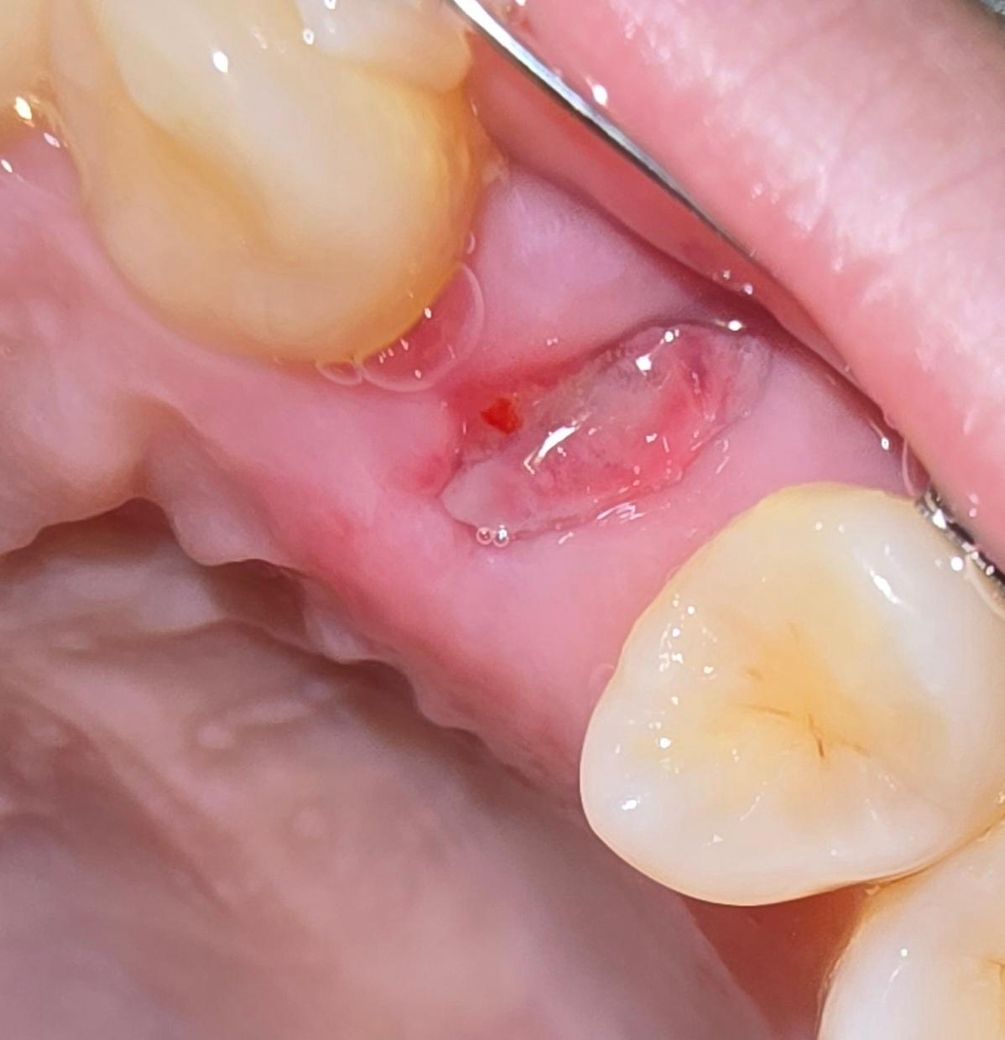

일주일 전에 교정으로 인해 상악 소구치 2개를 발치했는데요, 좌측은 하얀 조직이 생기며 잘 아무는 것 같은데 우측은 빨갛게 변하고 근처 잇몸 붓기가 있는 것 같아 혹시 염증이 생긴 건 아닌지 걱정됩니다. 둘다 잘 아물고 있는 것 맞을까요?

양치 과정에서 실수로 우측 발치 부위를 좀 건든 적이 있는데 그쪽이 딱 빨갛게 되니 더 걱정입니다.. 큰 통증은 없고 우측만 약간 욱신?거리는 느낌이 있는 편입니다.

• 1번 째 사진

사진상 치아를 발치한 자리에는 염증은 없어보이며 앞니쪽엔 구내염이 있어보이기도 합니다.

사진으로 봤을 경우 잇몸은 잘 아물고 있는것으로 보입니다.

붉은색이 띠는것은 혈병이 형성되면서 보일수 있는것이기 때문에 걱정하지 않아도 될것으로 생각됩니다.

약간 자극이 되어 발적이 있을 순 있으나 양쪽 다 치유 양호한 편입니다. 크게 걱정안하셔도 됩니다.